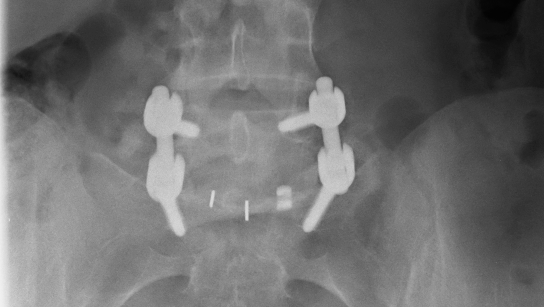

15+ Lumbar Spinal Fusion Hardware US. Adding bone graft to a segment of the spine. There are many approaches to lumbar spinal fusion surgery, and all involve the following process:

Anterior lumbar interbody fusion is a surgery to treat disc problems in the low back through an incision in the belly. It fuses (or connects) two or more vertebrae into one solid bone. Fusion locks together two or more bones to stop painful motion and correct their alignment. Lumbar fusion for a spinal condition is an effective back surgery to treat back pain.